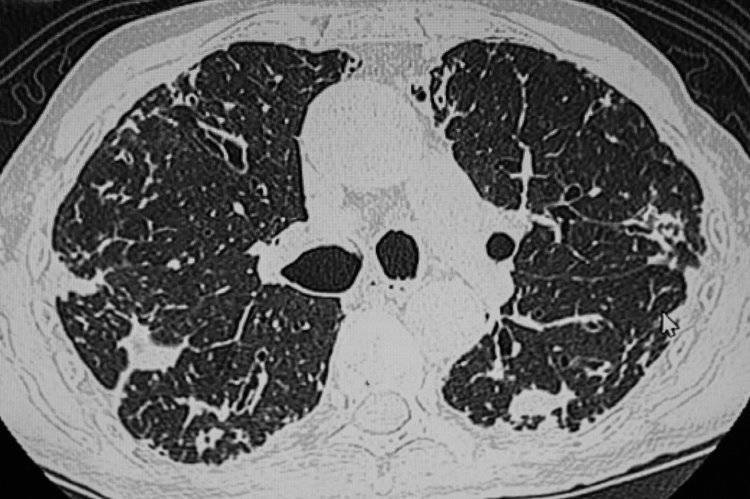

• 肺结节

肺结节是指肺部出现的≥3cm的病灶,在影像学里发扬为密度增高的暗影。

中国医学科学院肿瘤病院山西病院胸外科主任廉建红指出,目下查验仪器的精密度都很高,一些细微结节也能被实时发现,这些结节发刻下大部分是相比早期的,无需过分殷切。尤其是8mm以下的结节,一般都提议以随访为主。

提议年岁>45岁的成年东说念主每年进行一次肺部CT查验,通过查验可实时发现早期潜在的问题,对防治结节有贫困意象。